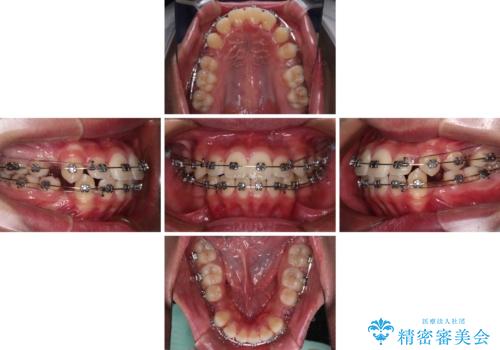

- 矯正装置

- メタルブラケット

- 治療期間

- 3年6ヶ月

- 治療回数

- 30回以上